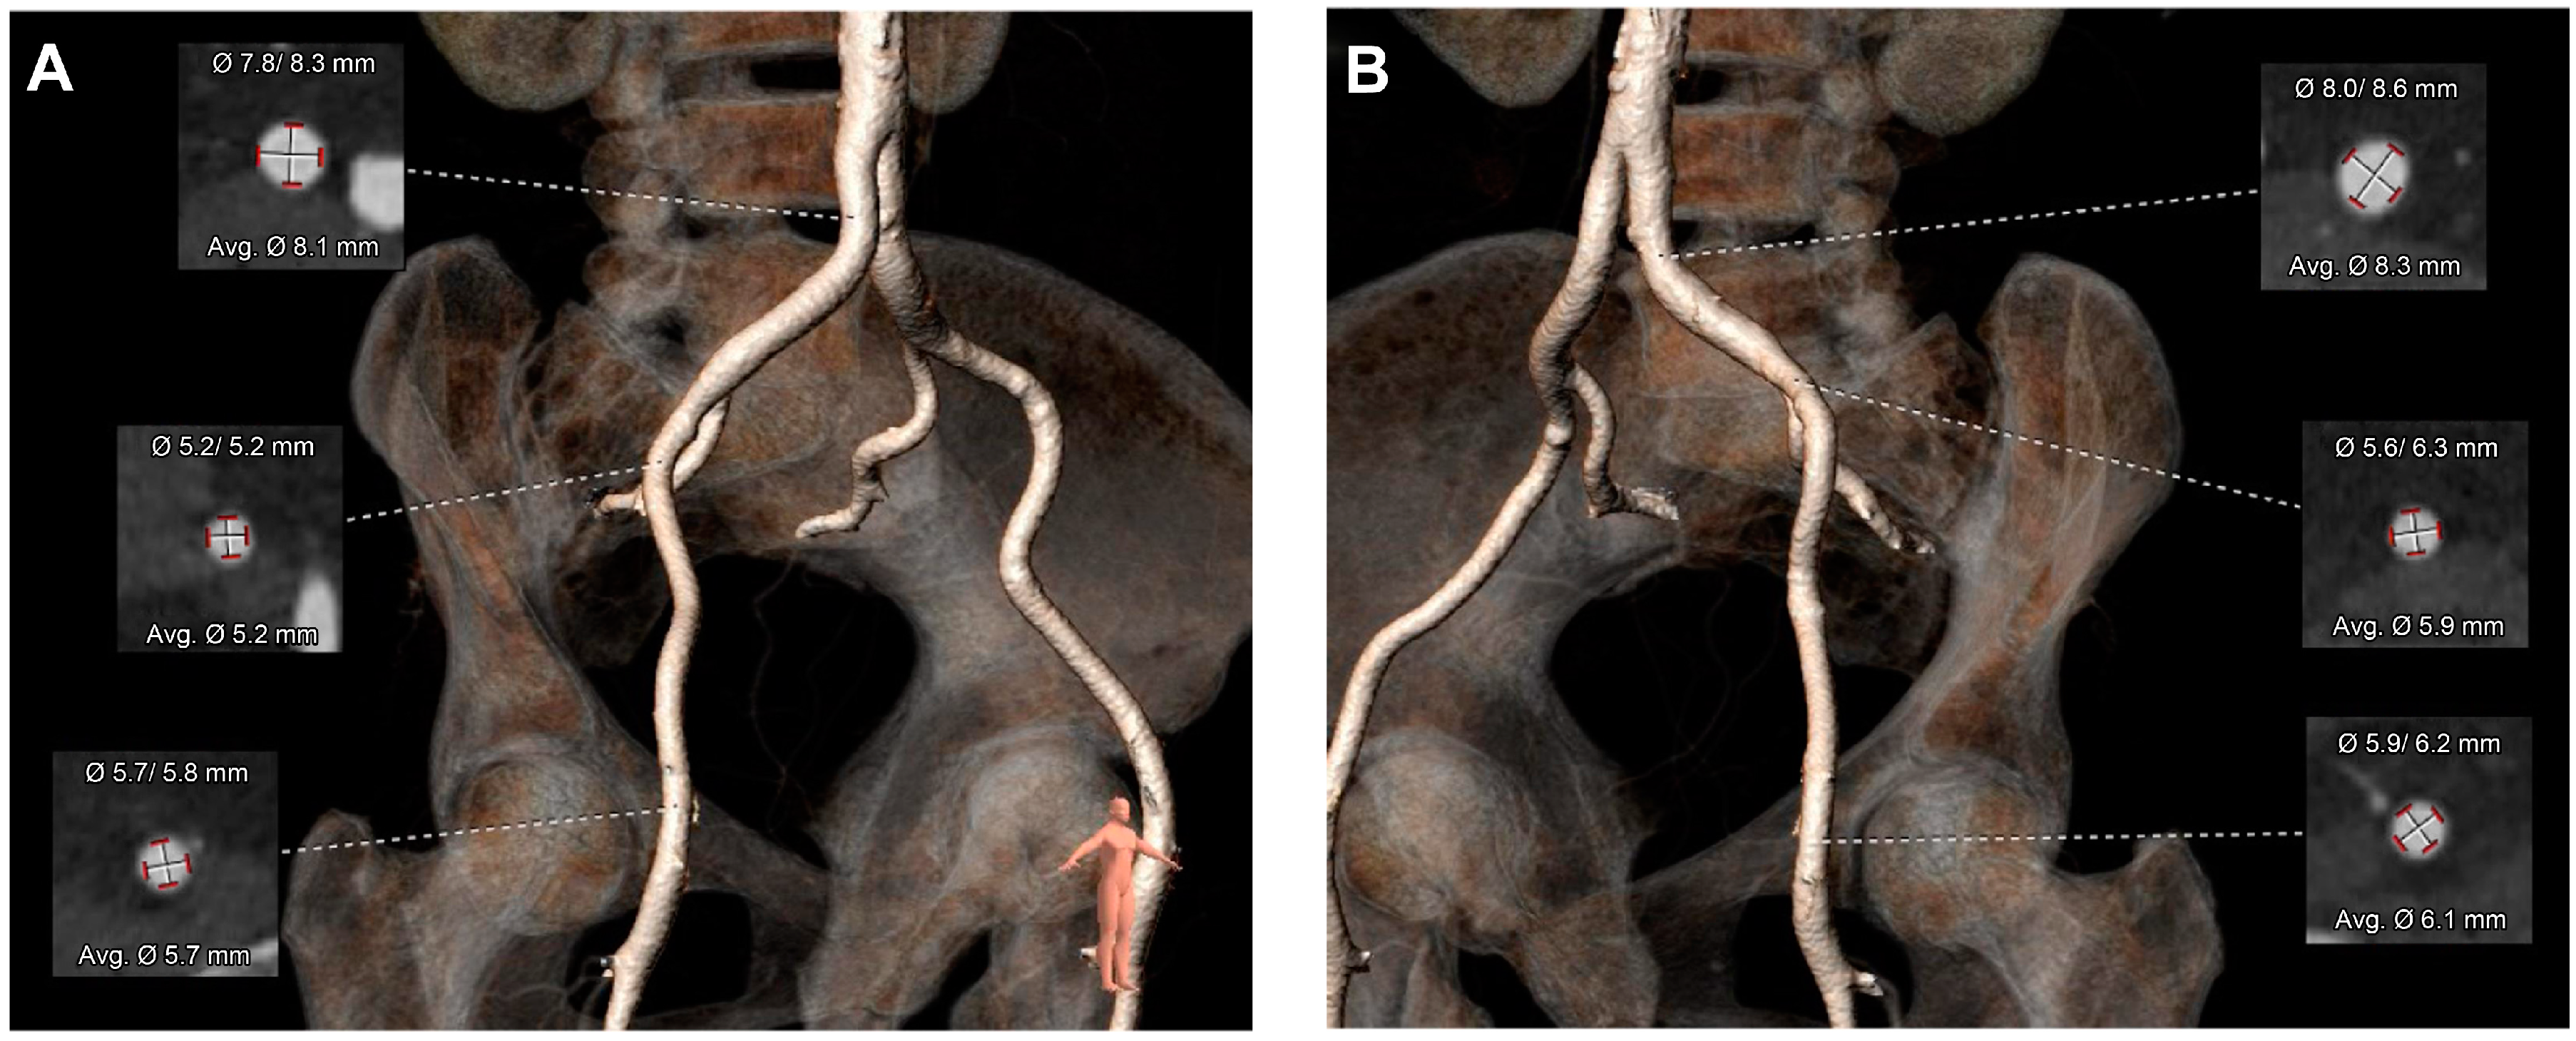

2. Case Presentation